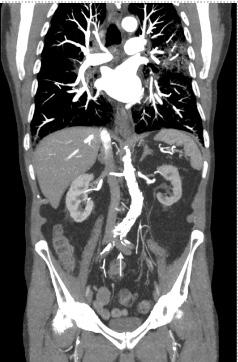

375 A Man with Sudden Onset Leg Pain and Weakness

J DeChiara, L Skinner

6.RudralingamV,FootittC,LaytonB.Ascitesmatters. Ultrasound. 2017;25(2):69–79.

7.BarrosLL,daSilvaJC,DantasACB,etal.Peritoneal Chlamydia trachomatis infectionasacauseofascites:adiagnosisnottobemissed. CaseRepGastroenterol. 2021;15(3):898–903.